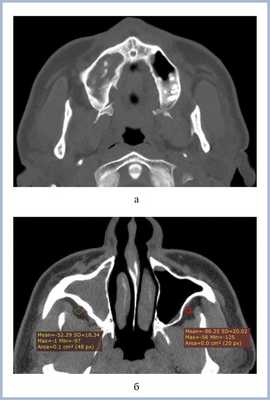

Воспалительные изменения слизистой оболочки верхнечелюстной пазухи, существующие в течение длительного времени, вовлекают в процесс костную стенку. На компьютерных томограммах отмечается утолщение костной стенки в костном режиме и появление «оптического эффекта» — уплотнение стенки в 1,5—3 раза за счет отека надкостницы — при просмотре в мягкотканом режиме (рис. 1, а, б) [9]. При одностороннем процессе, характерном для одонтогенного поражения, на контралатеральной интактной стороне такого эффекта не определяется.

Рис. 1. Рентгеновская компьютерная томограмма околоносовых пазух. Коронарная проекция: мягкотканное окно (а) и костное окно (б).

В костном режиме программы просмотра изображений утолщение костных стенок верхнечелюстной пазухи определялось в 21% случаев (рис. 2, 3), что указывает на хронический характер воспаления. «Оптический эффект» в мягкотканном режиме программы просмотра диагностических изображений определялся у 30,7% больных, что указывает на вовлечение надкостницы.